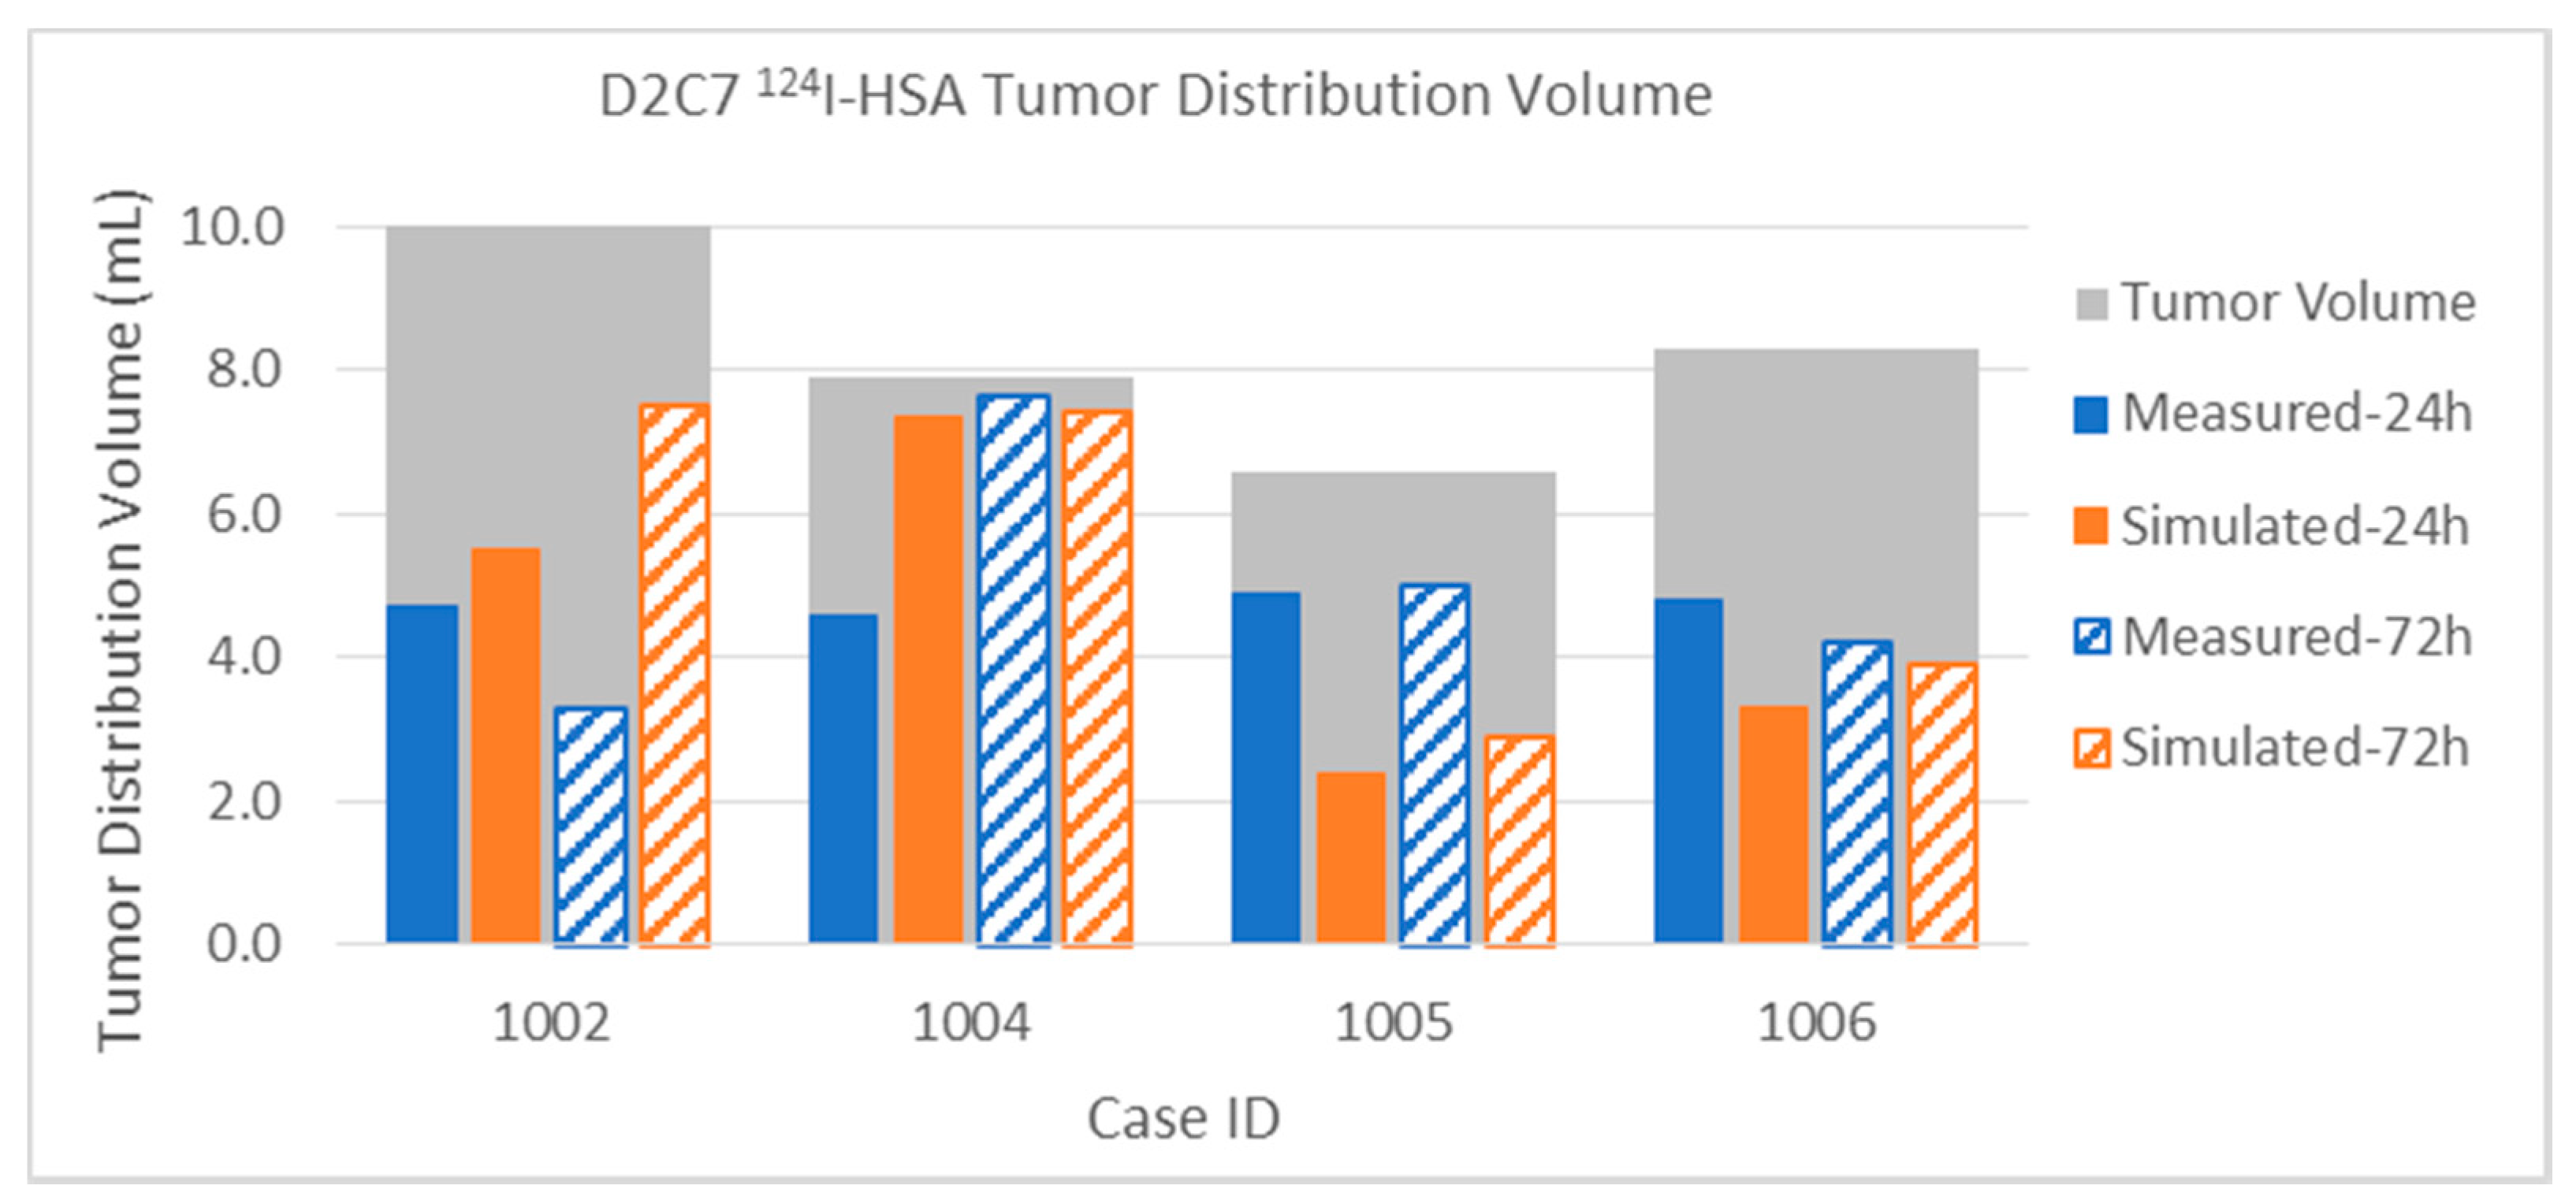

3.2.2. Tumor Distribution Volume

3.2.3. Error Measure

| D2C7 P1002 | Gad | Measured | 1.5 | 2.0 | 5.3 | 4.0 | 6.8 | 6.0 | 15.0% | 20.0% | 6.2% | 4.7% | 10.0 | 86.0 |

| 124I | Measured | 4.7 | 3.3 | 18.1 | 25.8 | 22.8 | 29.1 | 47.0% | 33.0% | 21.0% | 30.0% | 10.0 | 86.0 | |

| Simulated | 5.5 | 7.5 | 11.2 | 19.6 | 16.7 | 27.1 | 55.0% | 75.0% | 13.0% | 22.8% | 10.0 | 86.0 | ||

| D2C7 P1004 | Gad | Measured | 0.8 | 1.5 | 0.1 | 0.1 | 0.8 | 1.6 | 9.9% | 19.0% | 0.1% | 0.1% | 7.9 | 81.0 |

| 124I | Measured | 4.6 | 7.7 | 1.2 | 11.3 | 5.8 | 20.8 | 58.2% | 97.0% | 1.5% | 14.0% | 7.9 | 81.0 | |

| Simulated | 7.4 | 7.4 | 11.3 | 21.9 | 20.0 | 32.0 | 93.0% | 94.1% | 14.0% | 27.0% | 7.9 | 81.0 | ||

| D2C7 P1005 | Gad | Measured | 0.7 | 0.1 | 1.5 | 0.2 | 2.6 | 0.4 | 10.0% | 1.5% | 1.6% | 0.2% | 6.6 | 96.0 |

| 124I | Measured | 4.9 | 5.0 | 9.1 | 14.4 | 14.0 | 19.4 | 74.2% | 75.8% | 9.5% | 15.0% | 6.6 | 96.0 | |

| Simulated | 2.4 | 2.9 | 3.9 | 6.1 | 6.3 | 9.0 | 36.4% | 43.9% | 4.1% | 6.4% | 6.6 | 96.0 | ||

| D2C7 P1006 | Gad | Measured | 0.6 | 1.2 | 0.2 | 0.4 | 0.8 | 1.6 | 7.2% | 14.5% | 0.2% | 0.4% | 8.3 | 94.3 |

| 124I | Measured | 4.8 | 4.2 | 3.8 | 4.0 | 9.2 | 8.9 | 57.8% | 50.6% | 4.0% | 4.2% | 8.3 | 94.3 | |

| Simulated | 3.3 | 3.9 | 2.3 | 3.8 | 5.6 | 7.7 | 39.8% | 47.0% | 2.4% | 4.0% | 8.3 | 94.3 | ||